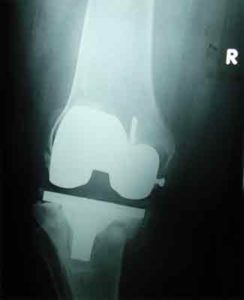

When an Artificial Knee Joint fails, a second operation is required to replace the failing joint. This procedure is called a Revision Joint Replacement.

Mechanical loosening means that the attachment between the artificial joint and the bone becomes loose due to some reason (other than infection). Loosening can occur after a period of extensive use of the joint. This could be as much as 10 to 15 years. This is one reason that surgeons like to wait until absolutely necessary to put in an artificial joint. The younger you are when an artificial joint is put in, the more likely it is that the joint will loosen and require a revision.

If the artificial joint gets infected, it has to be removed to cure the infection. Once the infection settles down a Revision Total Knee Replacement Surgery is done for the patient. Till the time the new implant is put, a cement spacer impregnated with antibiotic is put inside the Knee to give it stability.

If the infection does not come under control, a new implant cannot be inserted and hence fusion of the Knee is the only option.

A fracture may occur near an artificial joint. It is sometimes necessary to use a new artificial joint to fix the fracture. For example, if the femur (thighbone) breaks where the prosthesis attaches, it may be easier to replace the femoral part of the artificial joint with a new piece that has a longer stem that can hold the fracture together while it heals. This is similar to fixing the fracture with a metal rod.

It is not uncommon for the Knee Joint to be either too tight or too loose. If the Knee Joint is too loose, it can cause unsteadiness and pain. If the joint is too tight, the Knee is usually painful and doesn't have a good range of motion. In situations like these a revision becomes necessary.

With the rise in Knee Joint Replacements, surgeons have begun to see wear in the plastic parts of the artificial joints. In some cases, if the wear is discovered in time, the revision may only require changing the plastic part of the artificial joint. If the wear continues until the metal is rubbing on metal, the whole joint may need to be replaced.

Finally, the metal of the artificial joint can break due to the constant stress that the artificial joint undergoes every day. In weight-bearing joints like the Knee, this is greatly affected by how much you weigh and how active you are.